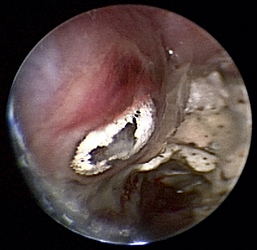

Rhinoscopic sequence imaging of TNC debridement of a feline caudal nasal and nasopharyngeal adenocarcinoma is depicted in Figures 19-63 through 19-69.

image

Figure 19-63 Transnares curettage sequence: feline nasal adenocarcinoma of the right caudal nasal cavity and nasopharynx, evaluation of the tumor extent, tumor debridement, and reevaluation of lumen patency after the procedure.

Figure 19-69 The nasal passage and nasopharynx is clear; restoration of patient nasal breathing has been accomplished with minimal trauma.